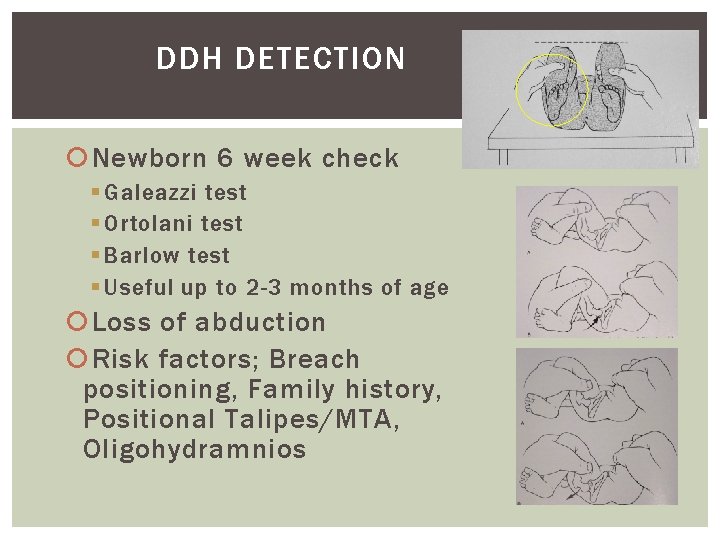

DDH DETECTION Newborn 6 week check § Galeazzi test § Ortolani test § Barlow test § Useful up to 2 -3 months of age Loss of abduction Risk factors; Breach positioning, Family history, Positional Talipes/MTA, Oligohydramnios

DDH